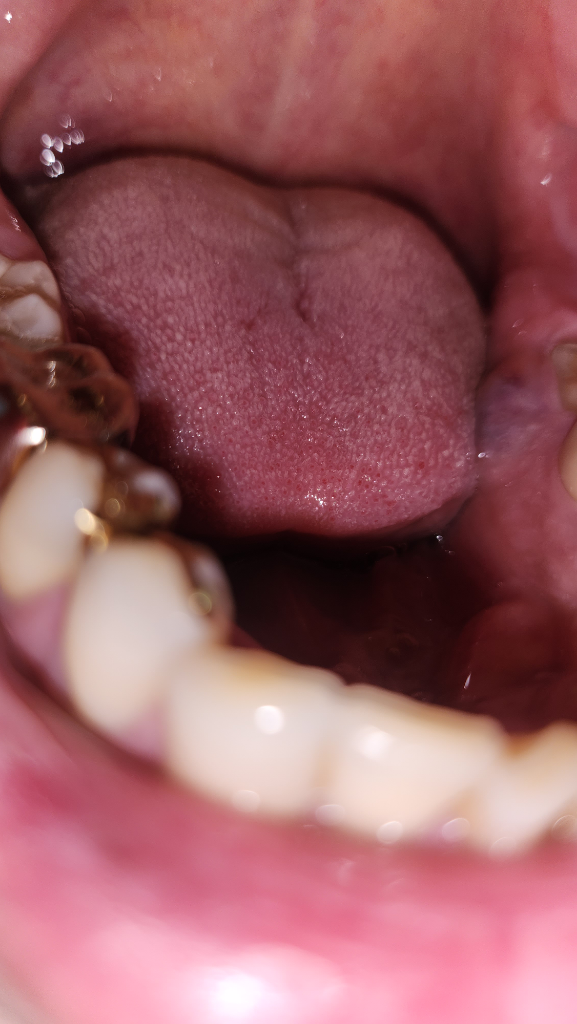

바깥쪽 볼은 손바닥을 대었을때 부은 느낌이 들고 치아 옆쪽 부분은 사진처럼 부음 증상이 생겼습니다

• 2번 째 사진